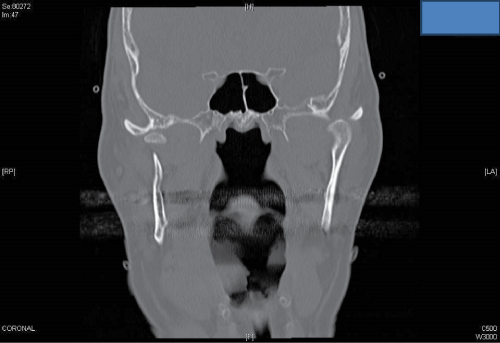

A C.T. scan revealed left condylar head subluxation and right condylar head fracture with medial displacement. The margins of the fracture were fresh according to the radiologist’s report, which excludes the possibility of a pre-existing fracture (Figure 2a,2b).